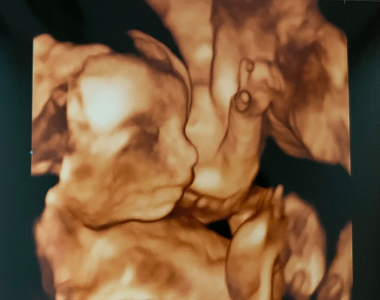

Petra si ve 26. TT ze 4D ultrazvuku přivezla krásné fotky i video

Petra byla v posledním týdnu hned na dvou vyšetřeních. Na klasické kontrole se Ondráškovi moc fotit nechtělo, ale 4D ultrazvuk si zřejmě užil, akční b...